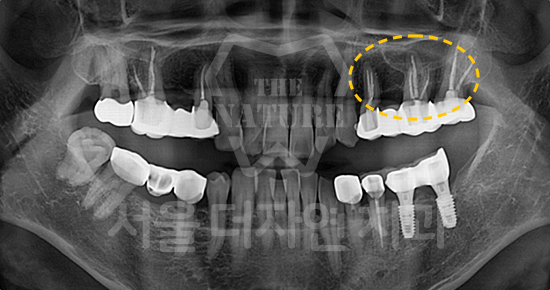

#Sinus Lift

-

BEFORE: 2021.02.01

AFTER: 2021.05.13

#Maxillary Bone Grafting

BEFORE: 2021.11.02

AFTER: 2022.01.19

Treatment outcomes may vary by patient,

and side effects may occur.

These images were taken under the same conditions,

and were published with the patient's consent.